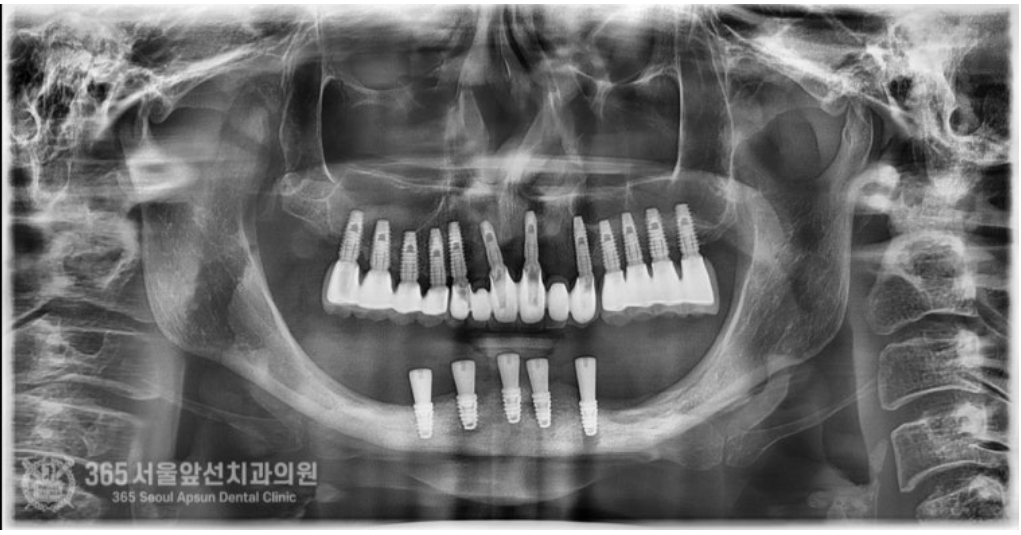

아래쪽에 임플란트 틀니를 썼었는데, 전체 임플란트 치료를 받고 싶어서 치과에 갔더니 뼈가 없어서 임플란트가 불가능하다고 판정받았어요. 촬영일시 : 2024.07.07. 처음 내원 당시 엑스레이 사진입니다. 촬영일시 : 2024.07.07. 사진에 노란색 표시를 한 곳이 신경관입니다. 보다시피 어금니 부위에는 뼈가 하나도 없습니다. 이 정도 뼈 상태라면 1000명의 환자분이 오신다면 그 중 단연코 1등으로 뼈가 안좋으신 상태 정도 됩니다. 기존의 임플란트는 제거를 해야하고, 이후 신경관을 피해서 5개의 임플란트를 식립하기로 했습니다. 촬영일시 : 2024.07.07. 수술 전 CT 사진으로 신경 구조물에 대한 정확한 사전 파악 후 수술에 들어갑니다. 왼쪽 아래턱 부위의 신경이 손상되지 않게 조심스럽게 수술을 진행했습니다. 오른쪽 아래턱 부위도 동일하게 신경이 손상되지 않게 조심스럽게 수술을 진행합니다. 기존 임플란트는 상태가 좋지 않아서 제거했습니다. 촬영일시 : 2024.07.07. 촬영일시 : 2024.11.16. 임플란트 수술 후 엑스레이입니다. 원하는 위치에 정확히 임플란트가 식립되었습니다. 임플란트가 뼈와 단단하게 굳으면 본을 떠줍니다. 정교한 보철물을 위해선 정확한 본뜨기 작업은 필수겠죠? 촬영일시 : 2024.11.16. 완성된 보철물입니다. 촬영일시 : 2024.11.16. 대략 4개월에 걸쳐 치료를 완료해드렸습니다. 환자분께서는 아주 만족하셨습니다. 정확한 임플란트 수술을 통해 신경 손상없이 성공적으로 마무리할 수 있었습니다 ㅎㅎ 촬영일시 : 2024.07.07. / 2024.11.16. 보철물 장착 전후의 입술 모습의 변화를 볼 수 있습니다. 입술이 볼록하게 지지받아서 자연스러운 안모로 변화했습니다. 촬영일시 : 2024.07.07. / 2024.11.16. 전후 구강내 사진입니다. 잇몸뼈가 많이 없으셔서 잇몸 부위를 핑크색이 나는 재질로 채워드렸습니다. 임플란트 불가능 판정을 받으셨던 환자분이신데 치료가 잘 마무리 되어 뿌듯했습니다 ㅎㅎ 신경관이 근접한 고난이도 임플란트 치료지만 충분한 경험과 지식이 있다면 치료가 가능하니 걱정 안하셔도 되겠습니다. 지금까지 365일 열린 가까운 서울대학교 치과병원을 지향하는 365서울앞선치과였습니다. 감사합니다. [ 치료기간 : 2024년 7월7일 ~ 2024년 11월 16일 ] ※ 365서울앞선치과의원의 모든 포스팅은 각 진료과 의료진이 직접 작성합니다. 365서울앞선치과의원 블로그의 임상 케이스 게시물은 환자분께 의학적으로 정확하고 상세한 정보를 드리기 위해 각 진료과 의료진이 직접 작성하며, 모든 증례 사진은 본원 의료진이 직접 시술한 증례를 촬영한 것으로, 의료법 제23조, 제56조에 의거하며 환자분의 동의를 얻어 포스팅에 사용하였습니다. 또한 해당 케이스는 본 환자분의 치료 결과이며, 환자 상태에 따라 치료의 결과는 달라질 수 있습니다. |